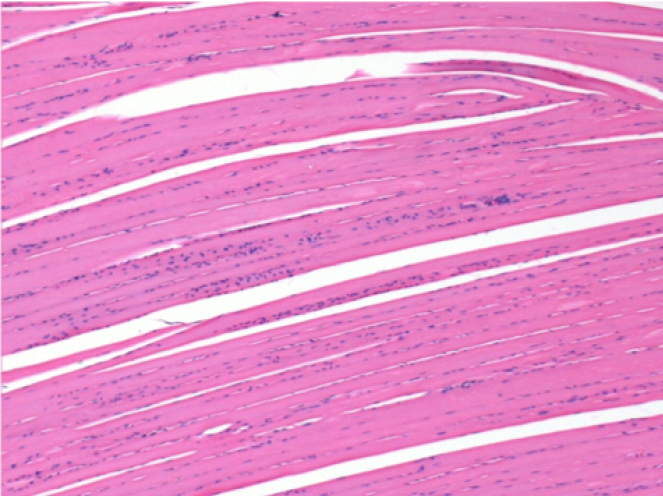

10 días después de la inyección de Endopeel 0,1 ml en el músculo pretibial derecho.

Aquí puede ver la formación de las vacuolas que están rodeadas de linfocitos. Las vacuolas son diferentes a la necrosis tisular. La presencia de linfocitos está relacionada con la permeabilidad de las membranas celulares.